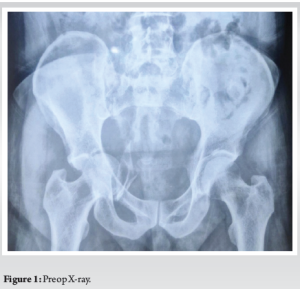

Xray (Fig. 1) and computed tomography (CT) scan (Figs. 2 and 3) were done to find out that he had an isolated Quadrilateral plate fracture with intrapelvic dislocation of the head femur with a napkin ring constriction around the dislocated head femur. However, both the anterior and posterior acetabulum columns were intact.

Case Report: A 55-year-old male patient presented to our outpatient department with 5 month old neglected post-traumatic central dislocation of the hip with a quadrilateral plate fracture. Initially, ORIF with infrapectineal plating was planned by anterior intra-pelvic approach. But despite best efforts (lateral and longitudinal traction along with reduction tools and maneuvers) it was not possible to reduce the head femur back into the native acetabular floor due to the long-standing napkin ring constriction. It was decided intra-operatively to proceed with THA. The patient was subsequently repositioned for THA using a standard posterior approach. The head femur was removed piecemeal and the medial wall defect was reconstructed using contoured titanium mesh with impaction bone grafting and rest THA was done in the usual manner. The patient was mobilized from 2nd post-operative day and allowed partial weight bearing with gradual progression to full weight bearing by 3rd week. He could return to his daily activities by 6 months and had a Modified Harris Hip Score of 91 in 1 year follow-up. Radiographs revealed well incorporation of the bone graft with no evidence of loosening. The patient didn’t have any complications such as infection. Heterotopic ossification or dislocation.